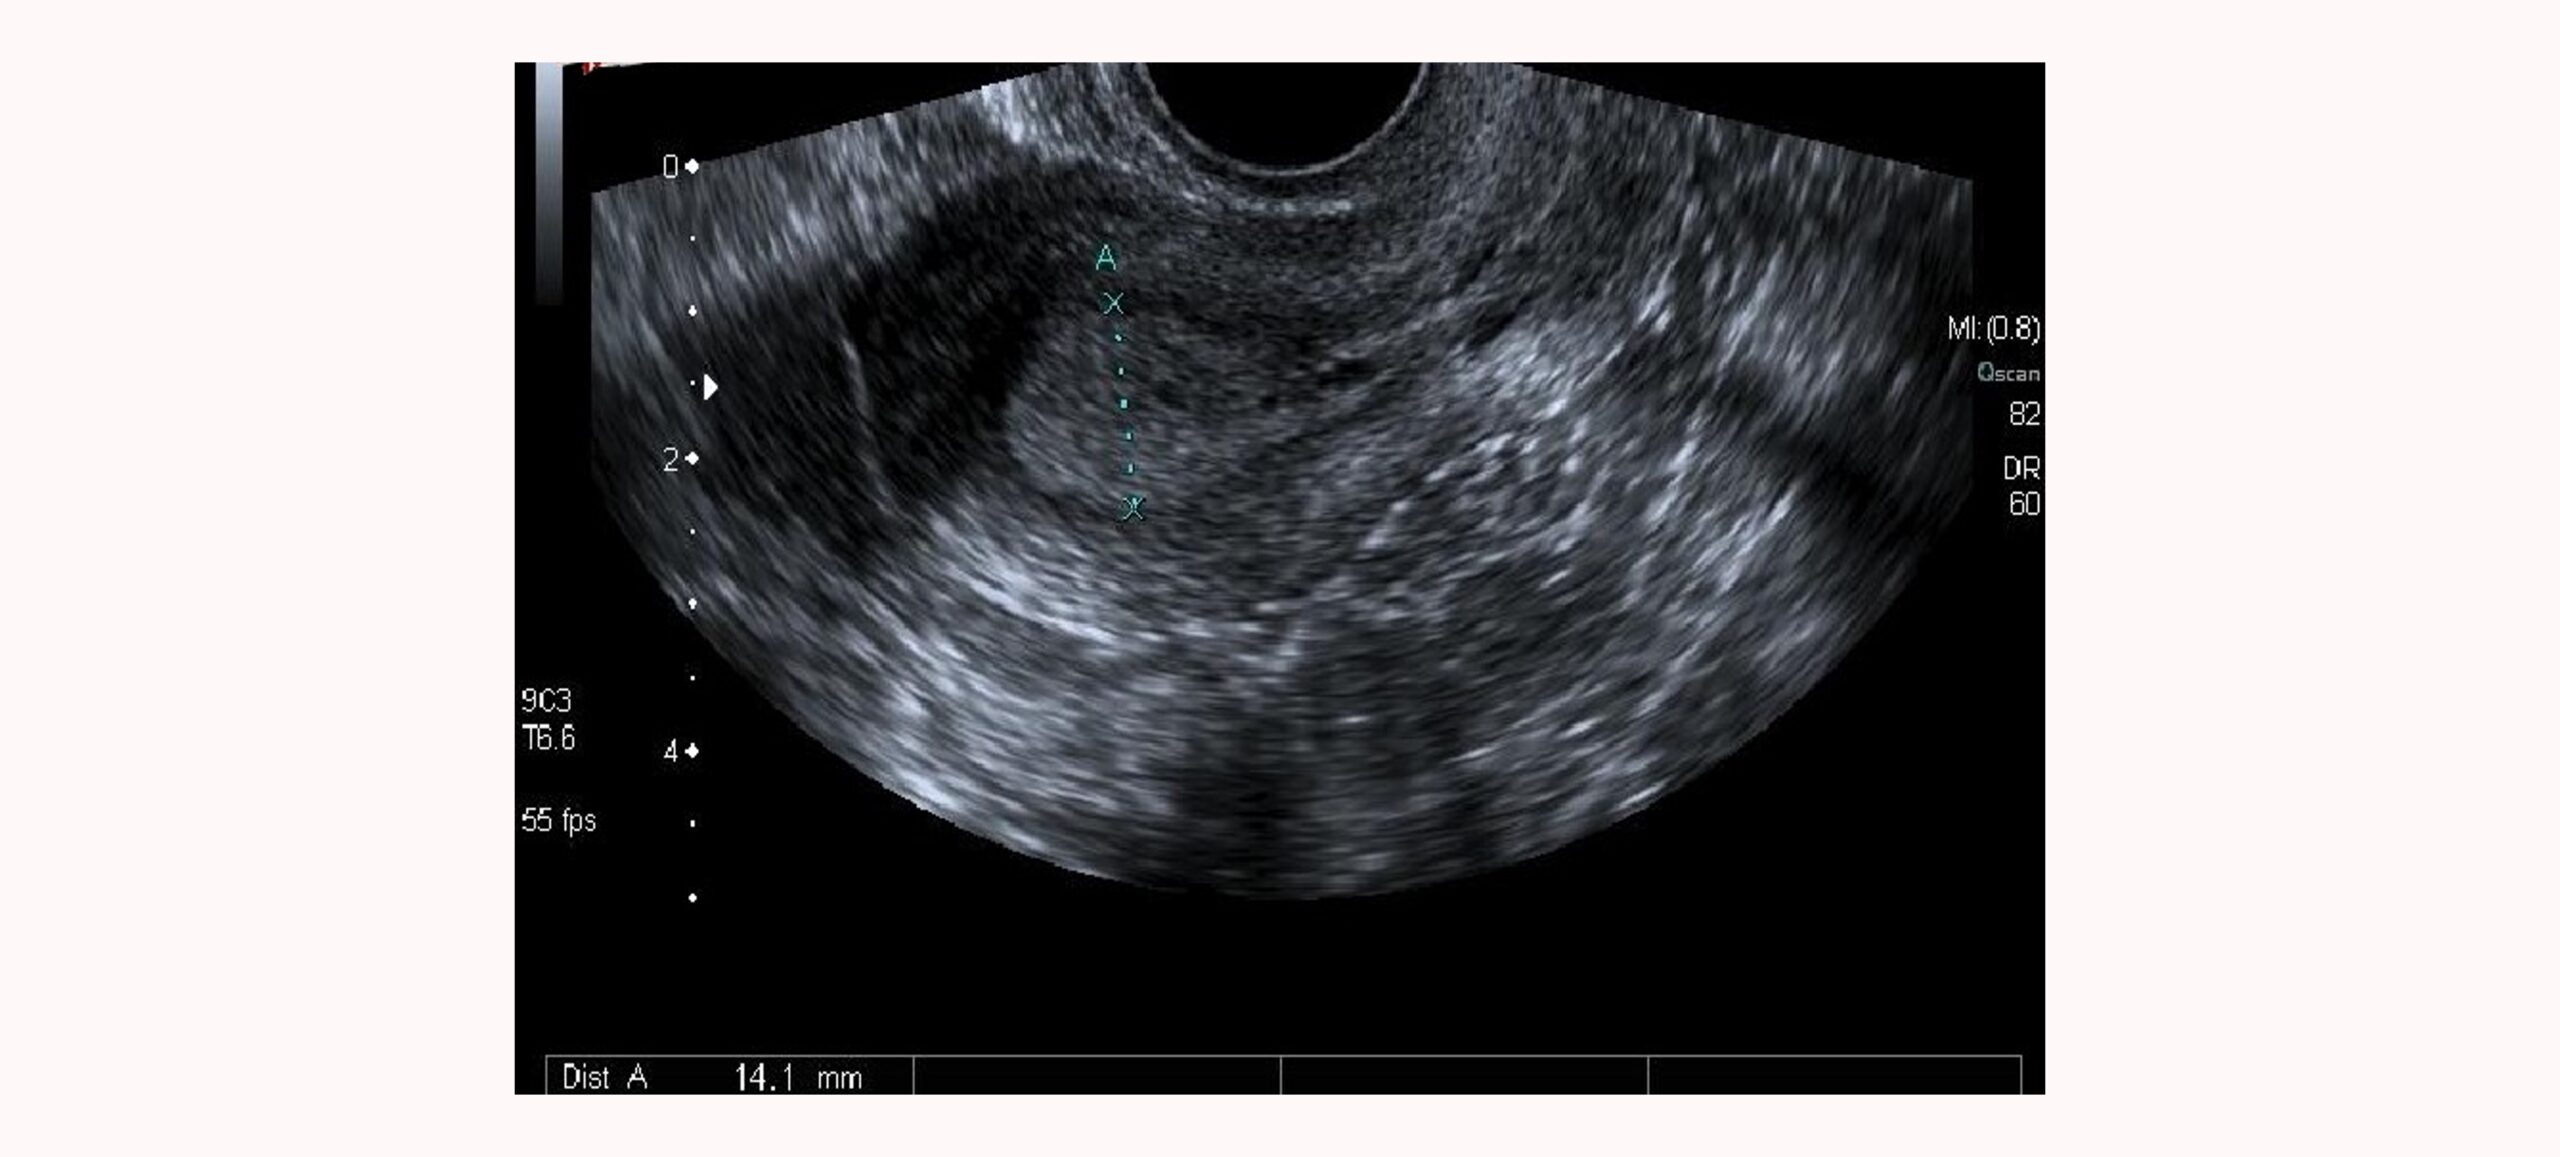

Mediante la ecografía medimos el grosor endometrial y a pesar de ser útil, a veces resulta insuficiente para predecir la idoneidad del endometrio para la implantación.